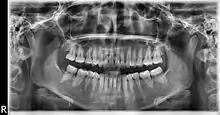

Ortopantomografía

La ortopantomografía o radiografía panorámica es una técnica radiológica que representa, en una única película, una imagen general de los maxilares, la mandíbula y los dientes. Por tanto, es de primordial utilidad en el área dentomaxilomandibular.

Su papel en el diagnóstico odontológico, no solo de los dientes sino también del maxilar y mandíbula, es fundamental. Sin la ortopantomografía el odontólogo perdería una gran ayuda en la mayoría de las especialidades de su campo. Prácticamente es utilizada de forma sistemática en odontología, llegando a ser un arma diagnóstica rutinaria. El valor diagnóstico de la ortopantomografía en cirugía bucal, implantología, ortodoncia, periodoncia y en patología oral y dental está claramente demostrado.

El término de radiografía panorámica es el más comúnmente utilizado, ya que la radiografía resultante muestra una visión panorámica de la cara y parte inferior de la cabeza. Laudenback describe la ortopantomografía como uno de los inventos radiológicos más originales de los últimos decenios. El 40% de los hallazgos patológicos principales y secundarios se descubren a partir de ella. Amplía el campo de diagnóstico en un 70% y reduce la dosis de radiación de la superficie cutánea en un 90% con respecto a las series radiográficas periapicales.